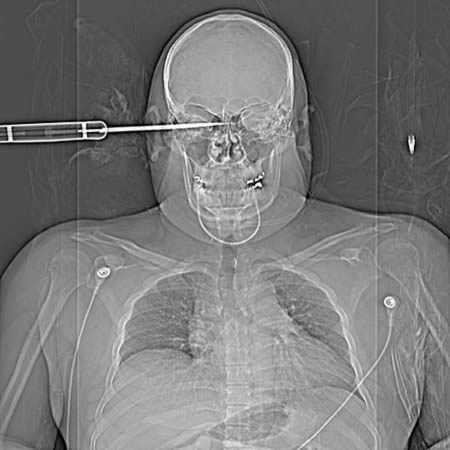

Зань Бин хэмээх 15 настай хүү жадаар хичээллэж байгаад хөмсөгний дунд хэсэгтээ санамсаргүйгээр зоожээ. 50 см урт энэхүү жад нь хүүгийн тархинд хүрээгүй өнгөц зоогдсон болохоор амьд гарсан байна. Зань хүү энэ талаараа: Ангийнхаа гурван хүүхэдтэй бэлтгэл хийж байсан. Тэгтэл гэнэт л толгой аймаар өвдөөд цус гарсан. Тэрнээс цаашаа юу болсныг санахгүй байна. Ангийнхан намайг 4 цаг яваад очдог Чаншагийн эмнэлэгт хүргэсэн байна лээ. Сүүлд нь толгойд зоогдсон жадаа харахад эвгүй санагдсан гэж ярьжээ.

Таны харж байгаа энэ зураг бол 15 настай нэгэн хүүгийн тархины рентген зураг. Хүүг хоёр найзтайгаа байхад нь дээрмийн хэрэг гарсан бөгөөд хүү энэ хэргийг таслан зогсоох гэж байгаад хутгалуулсан байна. Гэсэн ч хүү 10 сарын дараа бүрэн эдгээд зогсохгүй жинхэнэ гавал залуу болжээ. Хэрвээ хүүгийн хутгыг авах гэж оролдсон бол газар дээрээ нас барах байсан бөгөөд хутгыг хөндөөгүй нь сайн хэрэг хэмээн эмч нар тайлбарлаж байна.